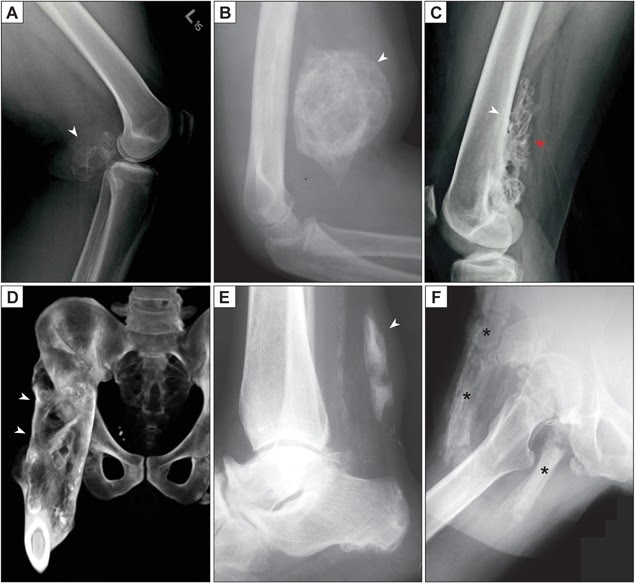

- X quang đặc hiệu nhưng không nhạy trong cốt hoá lạc chỗ giai đoạn sớm. Có thể mất 3-8 tuần để xương lạc chỗ hiển thị trên phim chụp X-quang. Xương lạc chỗ được mô tả là trông như “mịn như lông” (fluffy) hoặc “giống như bắp rang bơ” (popcorn-like). Giai đoạn ổn định đặc trưng bởi hiện tượng phân vùng mô học với lớp vỏ ngoài xương trưởng thành điển hình.

- Một số phân loại mức độ cốt hoá lạc chỗ trên X quang: Phân loại của Brooker cho khớp háng (phân độ I-IV), Phân loại Hastings và Graham cho khớp khuỷu (phân độ I-II))

Cốt hoá lạc chỗ có thể xảy ra ở bất cứ đâu, nhưng những vị trí thường gặp nhất là những vùng dễ bị chấn thương, như khuỷu tay, đùi, vùng chậu hông, và vai. Cốt hoá lạc chỗ cũng có thể gặp ở đầu và cổ trong trường hợp chấn thương.